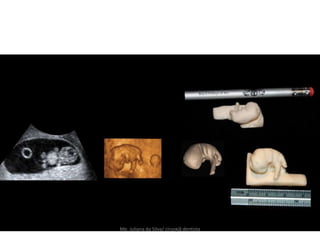

6 semanas                                8 semana

6 semanas aproximadamente